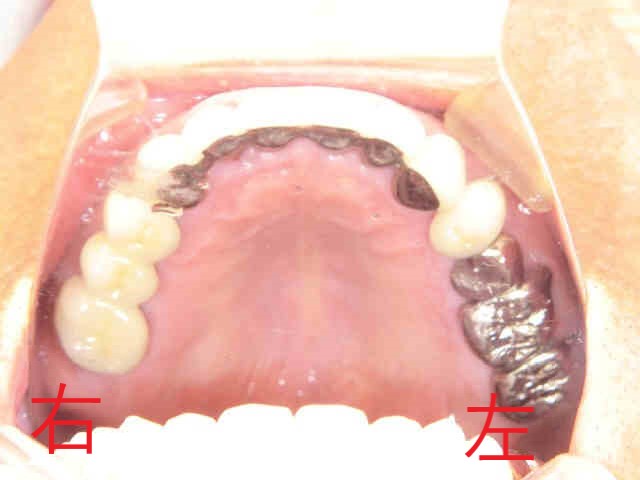

兵庫県三木市にお住まいの70代男性の患者様が、右下の被せ(黒色矢印)がグラグラして噛めないというお悩みで、〈みらい歯科クリニック〉に来院されました。なお、写真の掲載につきましては患者様の同意をいただいております。

また、患者様は“上顎前歯の出っ歯”を非常に気にしておられたため、丁寧にご説明したうえで、全顎的な治療計画を立案し、ご納得のうえで治療を開始させていただきました。写真で特に注目していただきたいのが、下顎前歯(青色矢印)です。

奥歯で噛んだ際に、下顎前歯が上顎前歯に隠れてほとんど見えなくなっている“深い噛み合わせ”の状態が確認できます。